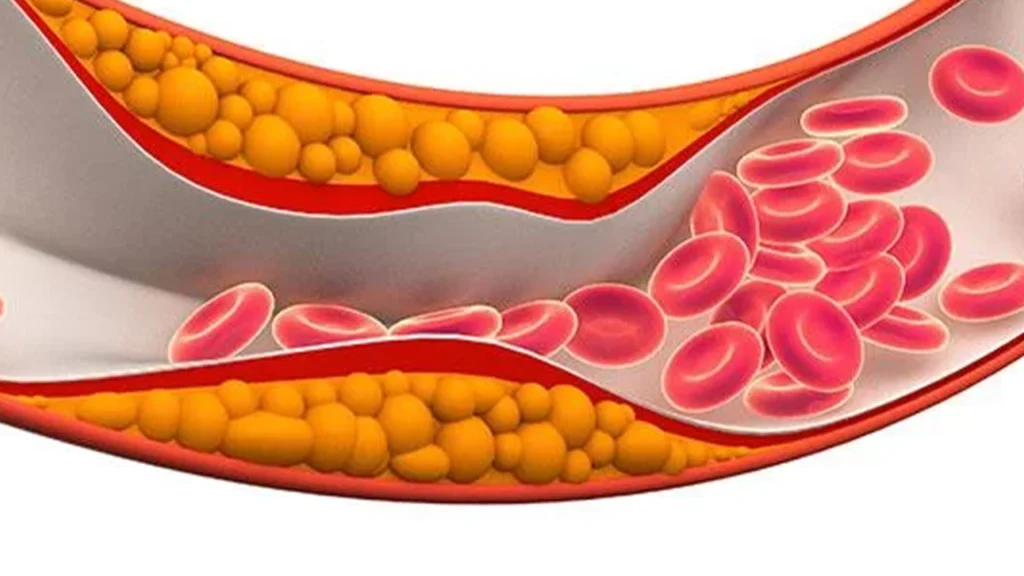

Tratamento individualizado para controle do peso, saúde metabólica e redução de riscos cardiovasculares.

Controle eficaz das gorduras no sangue para proteger o coração e prevenir doenças futuras.